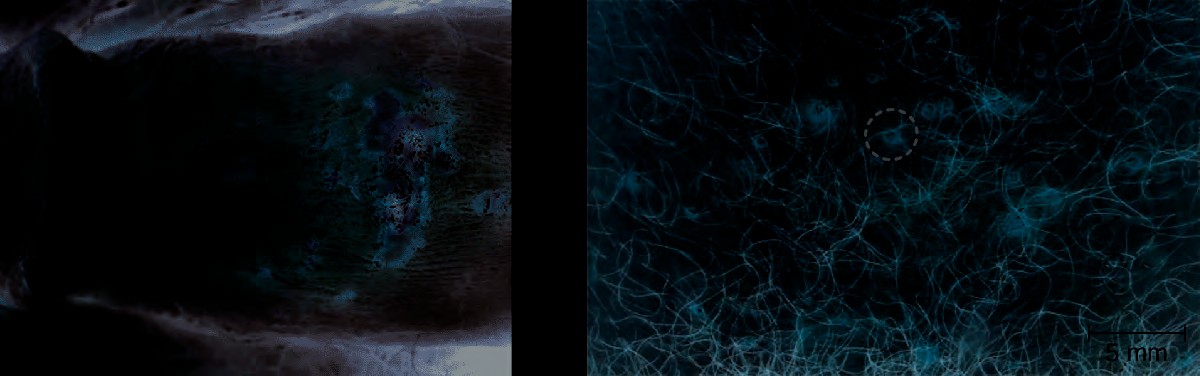

Figure 23.17 Genital herpes is typically characterized by lesions on the genitals (left), but lesions can also appear elsewhere on the skin or mucous membranes (right). The lesions can be large and painful or small and easily overlooked. (credit b: modification of work by Schiffer JT, Swan D, Al Sallaq R, Magaret A, Johnston C, Mark KE, Selke S, Ocbamichael N, Kuntz S, Zhu J, Robinson B, Huang ML, Jerome KR, Wald A, and Corey)